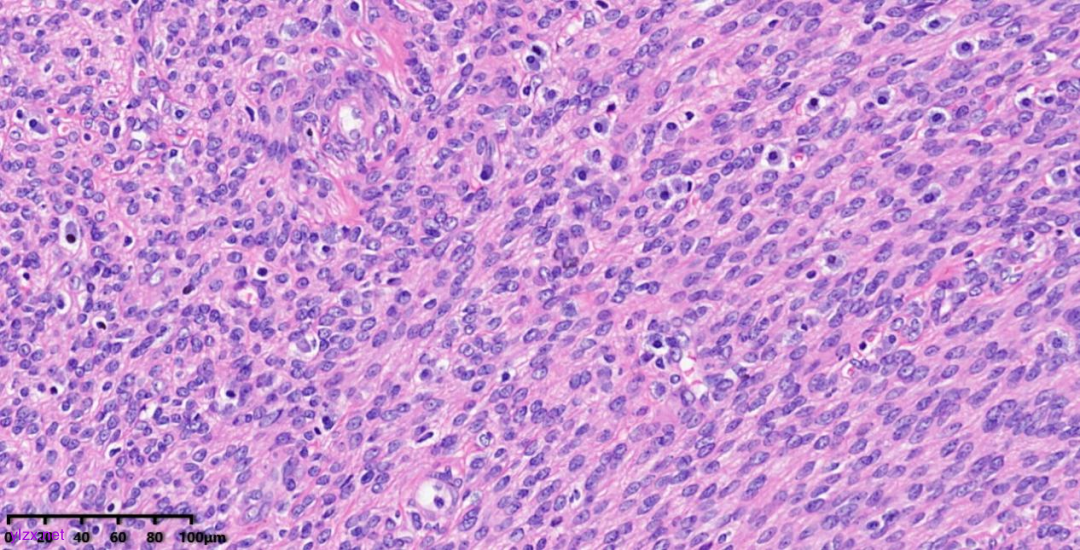

肿瘤细胞以梭形细胞、卵圆形细胞为主,部分为胞浆透亮的上皮样形态,透亮细胞界限较清,胞质淡染或胞浆丰富、嗜酸性,肿瘤内血管丰富,肿瘤细胞围绕血管周围片巢状、束状及放射状排列;肿瘤细胞核异型性不明显,核分裂像少见(<1个/50HPF),染色质开放,可见小核仁;肿瘤间质水肿、黏液变性,纤维胶原增生伴玻璃样变性。

图7~10 高倍镜下:梭形细胞、上皮样细胞组成的巢状、梁状结构,周围包绕纤细的薄壁毛细血管,肿瘤细胞呈放射状排列在血管周围,细胞界限较清,胞浆丰富、嗜酸性或透亮,细胞异型性不明显,核分裂像少见,细胞核呈圆形,染色质开放,可见小核仁;局部少量慢性炎细胞浸润。

PEComas通常表现为由梭形细胞、上皮样细胞组成的巢状、梁状结构,具有丰富的颗粒状、嗜酸性或透亮胞浆,圆形细胞核及细小核仁,巢状、梁状结构周围通常包绕纤细的薄壁毛细血管,肿瘤细胞呈放射状排列在血管周围。